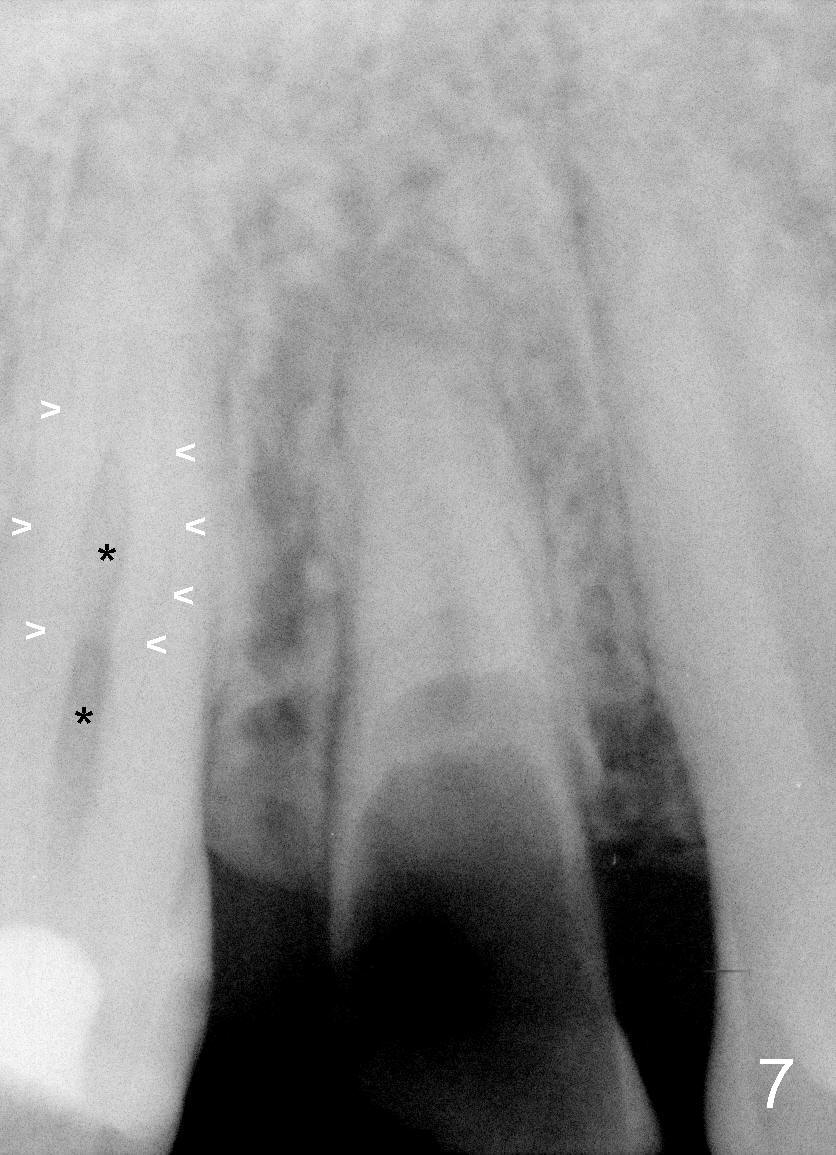

The tooth #4 has special canal morphology (Fig.6). In addition to the middle main canal (Fig.7 *), there are 2 lateral finer curved canals (arrowheads). The tooth #13 has the same canal patterns.